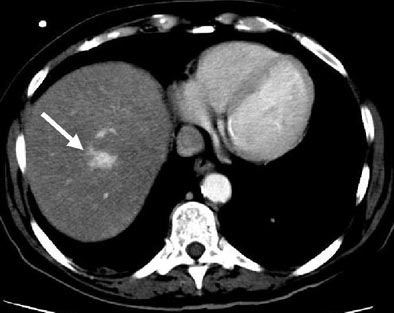

"This example of a type 4 hyperdense lesion on arterial-phase (CT) is not seen on the portal-venous phase, and the follow-up arterial-phase (scan) performed a few weeks later shows that the type 4 lesion had changed its morphology to a type 2 lesion, with a central hypodensity and peripheral hyperdense rim," he said.

| Immunocompromised patient after prolonged neutropenia with fever and candidemia. Type 4 lesion on arterial phase (above) is not seen on portal-venous phase (below). The lesion was also not visualized in arterial-phase CT performed a few weeks earlier (bottom), indicating a new lesion. |

![]() |